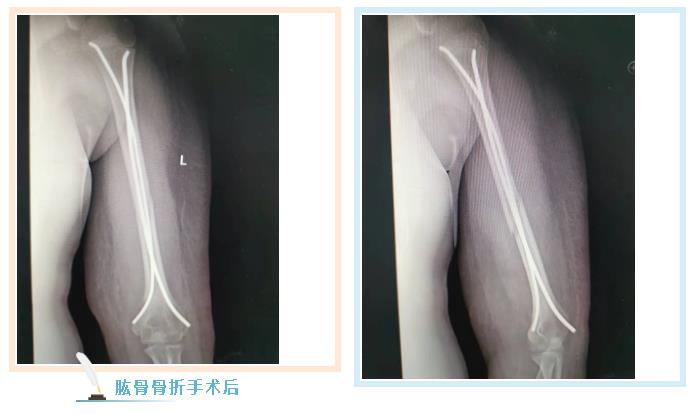

887700线路检测网骨伤二科副主任张永青仔细查看孩子患处,安排其进行放射拍片检查,结果为左侧桡骨颈骨折,根据孩子的骨折状况,张主任认为保守治疗很难做到理想复位,且复位后较难维持良好位置,可能会影响将来前臂的旋转功能,建议孩子尽快接受手术治疗,孩子的家长担心传统手术切口大,孩子所受痛苦多,犹豫不决,张主任与家长沟通,孩子要接受的不是传统的开放手术,而是“骨折闭合复位弹性髓内钉内固定”微创手术,手术只需要一个0.5-1厘米左右的切口就可以达到满意的效果,家长立即同意接受手术治疗。手术非常成功,术后第三天,周周出院。

张永青介绍,“弹性髓内钉技术”是儿童骨科界的一次革命,被誉为上帝赐予长骨骨折儿童的礼物,该项技术可在保护骺板不受损伤的前提下,利用多点固定的原理,微创、有效地治疗4-12岁的四肢骨折患儿,该技术利用钛合金或不锈钢良好的弹性、恢复力将作用于长骨的3个接触点转换成推力和压力,从而使骨折复位,有足够的力量抵抗骨折端移位作用,该方法不需要剥离骨膜和切开骨折端,不干扰骨骺生长,也不破坏骨折端血运,弹性固定、局部微动、创伤小、骨折愈合快,术后3周即可进行功能锻炼,术后1个月功能恢复正常。

887700线路检测网骨伤科自2018年在我市率先开展弹性髓内钉技术至今,共收治20多例四肢长骨骨折患儿,手术均为闭合复位或小切口辅助复位,在40分钟内完成,创伤小,恢复快,术后3-5天即可出院,大大减少了治疗费用和住院时间,减少了患儿的痛苦。